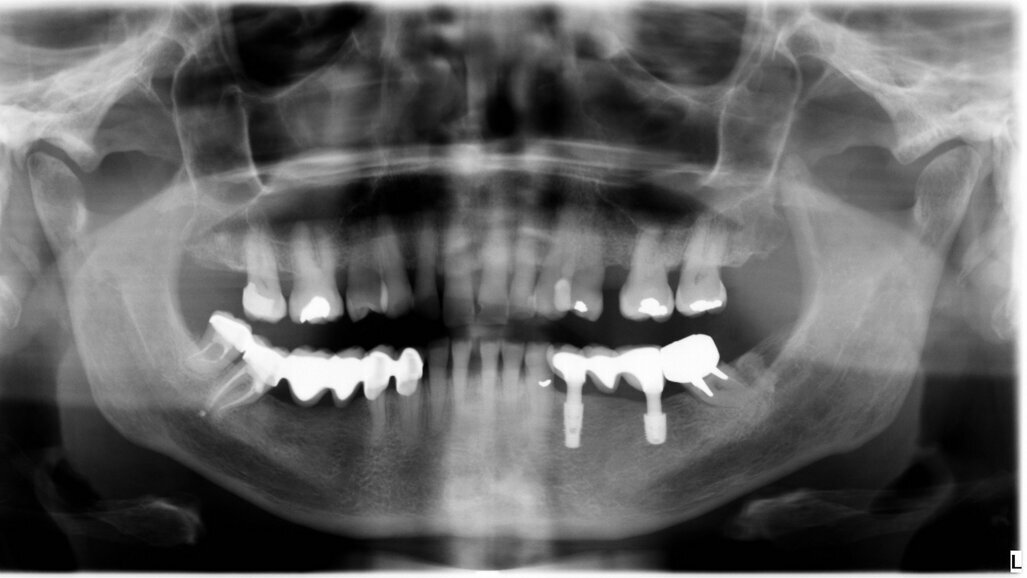

The female patient was 59 years old and had no noteworthy medical history, except for degenerative osteoarthritis of the left hip joint and compensated hypertension. She complained of chewing pain in the third quadrant. On physical examination, she presented with an old-fashioned bridge prosthesis with partial mobility, loaded on natural teeth. After radiographic evaluation with a dental panoramic tomogram of the dental arches, tooth #34 appeared devitalised, and tooth #37 appeared devitalised and a fused post-abutment was mesialised and considerably inclined (Fig. 1).

It was evident that tooth #34 had to be extracted. Despite the overload of tooth #37, the patient refused its extraction because it was not painful. We therefore proceeded with the separation of the existing bridge, maintaining the coverage of tooth #37 and the exposure of the edentulous part. Subsequently, the extraction of tooth #34 was performed. A CBCT assessment of the mandibular dental arch was performed, and the insertion of a 3.6 mm diameter and 9.0 mm long GTB implant in position #34 and of a 4.3 mm diameter and only 6.0 mm long GTB implant was planned (Fig. 2). This last choice was necessary not to avoid contact with the inferior alveolar nerve but because of the presence of a very high mylohyoid line and the consequent inclination of the lingual bone wall of the mandible below that line. We favoured the prosthetic axis of the implant rather than a greater length of the implant, which is obtainable by tilting it in a lingual–buccal direction. The surgical planning was performed according to the surgical protocol for GTB implants, which provides for the flattening of the knife blade ridge, the positioning of implants in the prosthetic axis and sinking the implant to the sub-crestal level of 1.5 mm. During surgery, we obtained an insertion torque of 25 Ncm in position #34 and of 20 Ncm in position #36 (Figs. 3a & b).

After three years, a panoramic radiograph was performed, highlighting excellent maintenance of the bone trophism and closure of the osteotomies created with the insertion of the implants (Fig. 5). Results of this type testify to the ideal biomechanical situation created above the implants, which are then protected from any bacterial infiltration, not only by the mucosa, which appeared stable and healthy, but also by the bone bridge created to protect the implant necks.

A further radiographic check was carried out seven years after the implants had been placed and showed growth of the bone level and the formation of a curved bone profile to support the interdental papillae, which is typical of natural teeth (Figs. 6a &b). Caries occurred under the crown of tooth #37, but the patient did not wish to have it treated. Upon physical examination, the soft tissue appeared stable and of excellent trophism.

After nine years, a new radiograph was performed which highlighted how the scallop had not only been maintained but even remodelled (Figs. 7a & b). The supra-implant bone appearance around the abutments presented a hyperdense and extreme continuity with the abutment neck, despite the non-punctual hygienic maintenance, highlighted by the state of the soft tissue and by the caries affecting tooth #37, then in the terminal stage (Figs. 8 & 9). After removal of the bridge, we tried probing, but it was absolutely impossible owing to the thickness of the soft tissue.